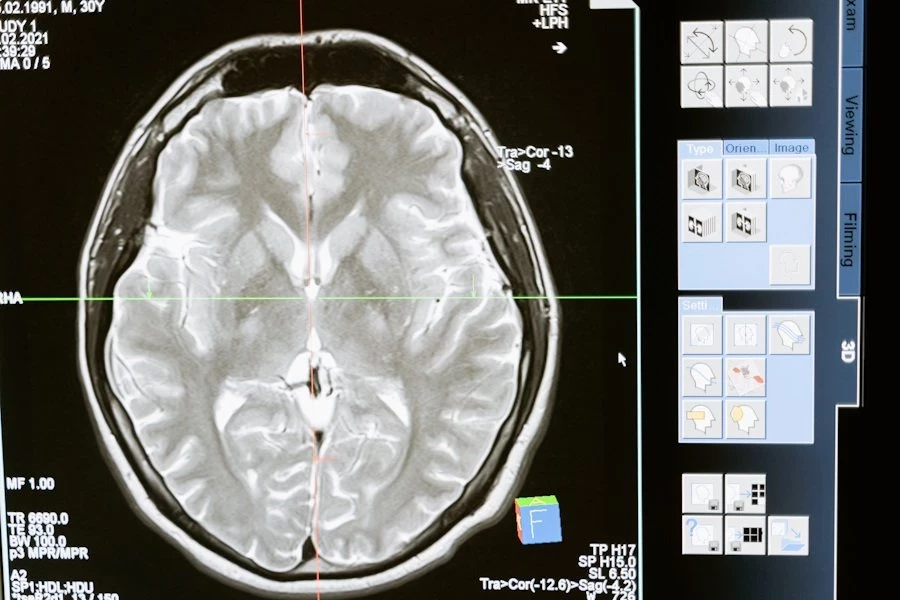

Как сон влияет на мозг: связь между апноэ и повреждением белого вещества

Ещё одна важная находка связана с уровнем кислорода в крови. Учёные выяснили, что снижение кислорода во время сна связано с увеличением гиппокампа и повреждением белого вещества мозга. Повреждённые области белого вещества, согласно исследованию, могут нарушать взаимодействие между различными участками мозга.